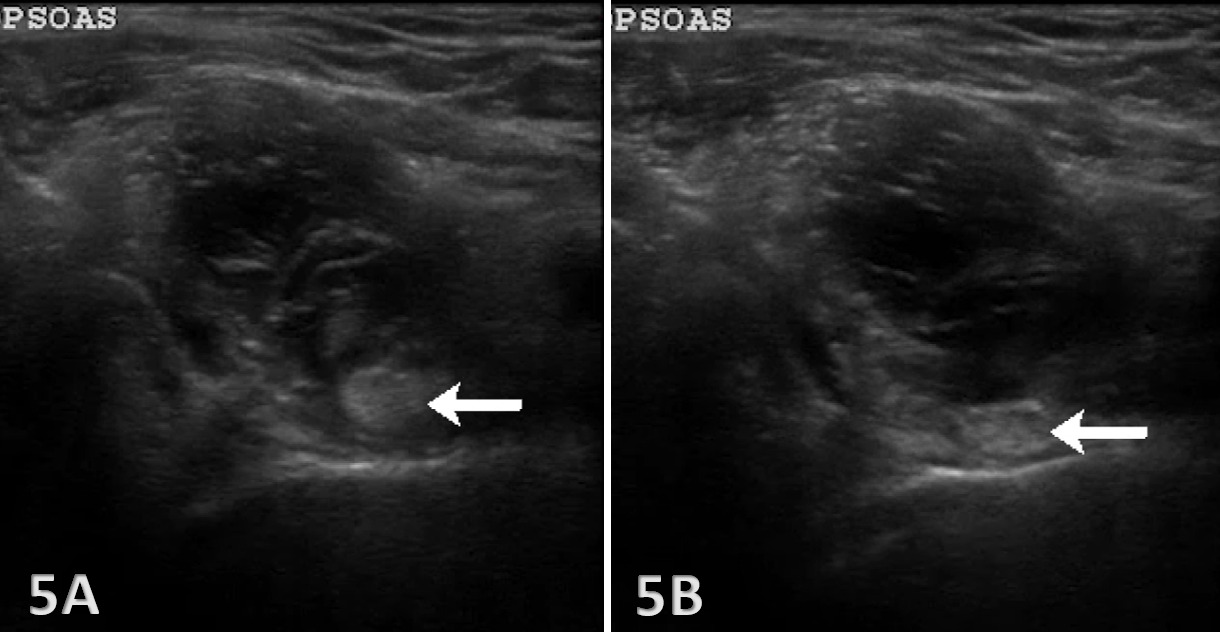

Bursitis: Iliopsoas bursitis may present as an anechoic or hypoechoic fluid collection between the iliopsoas tendon and the hip joint capsule. The bursa originates at the level of the femoral head and typically extends medially and possibly deep to the psoas major tendon and iliopsoas tendon.13 An iliopsoas bursitis will present as hip and groin pain. Bursal distensions rarely produce compression neuropathy of the femoral nerve; however, large distensions may extend into the pelvis along the iliacus muscle and may displace the pelvis structures.14 Management includes anti-inflammatory strategies and ultrasound-guided bursal injections.